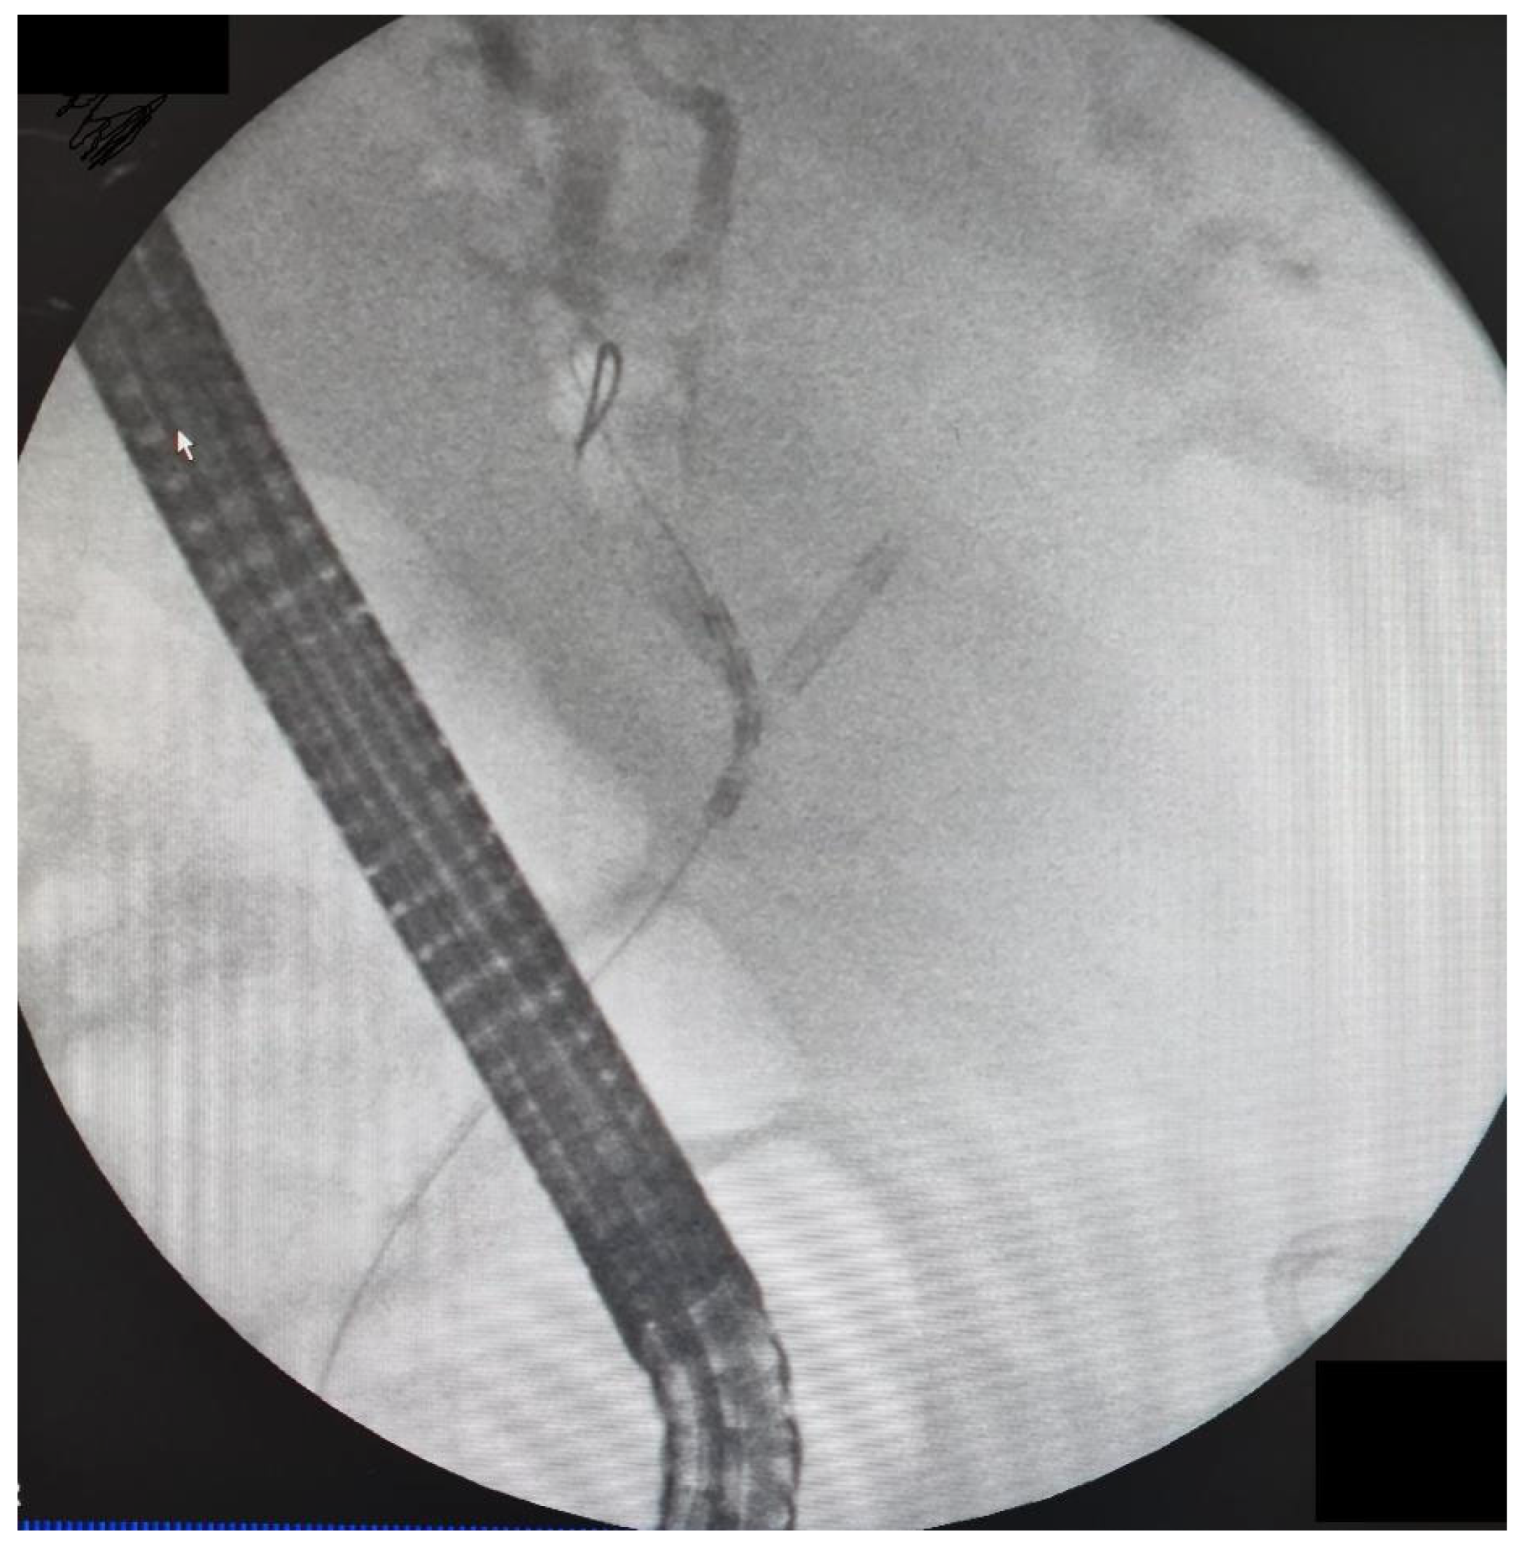

The data from 24 consecutive patients with bile duct stenosis due to non-resectable HC who underwent RFA with bile duct stenting in our department between 05.2020–05.2024 were collected retrospectively from electronic medical records and analyzed. Patients with malignant biliary stenosis had diagnoses of unresectable HC, PDAC in the head of the pancreas, and adenocarcinoma of the gallbladder. Inclusion criteria for RFA treatment included patients with recurrent mechanical jaundice due to cancer progression despite a previous biliary prosthesis. High-power radiofrequency ablation of the narrowed biliary segments, followed by reimplantation of SEMS, Amsterdam stents, or double pigtail (DPT) into their lumen, was performed in 24 patients (19 women and 5 men). The procedure was performed under intravenous sedation using a PENTAX-ED-34 and 10t2 duodenoscope. RFA was carried out with a power setting of 7–14 watts and a temperature of 75–80°C. The following stents were used for the procedure: uncovered SEMS (10x80 mm, 10x60 mm, 10x100 mm), Large Cell D-type stents (LCD) (10x60 mm), fully-covered SEMS (8x80 mm), Amsterdam-type plastic stents (12cm 10 Fr, 9cm 10 Fr, 12 cm 8.5 Fr, 12 cm 7 Fr), and self-expandable BIL-0-10-60-RP stents. Figures 2, 3, and 4 present the RFA catheter and stents’ configurations (Figure 2, Figure 3, Figure 4).

Figure 3. Stent-by-stent double SEMS configuration.